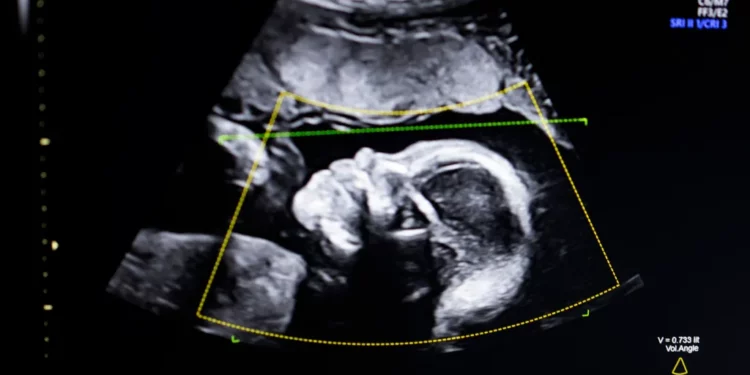

Produkti i BioticsAI është projektuar për të ndihmuar profesionistët e shëndetit gjatë ekzaminimeve prenatale, duke analizuar në kohë reale cilësinë e imazheve të ultrazërit dhe duke sinjalizuar nëse pamjet anatomike janë të plota dhe të përshtatshme për vlerësim. Në praktikë, kjo do të thotë më pak rrezik për skanime jo të sakta dhe më shumë mbështetje për mjekët dhe teknikët, sidomos në ambiente me burime të kufizuara ose me staf më pak të specializuar. Teknologjia përdor modele të trajnuara mbi një numër të madh imazhesh fetale, me synimin për të standardizuar cilësinë e ekzaminimeve dhe për të reduktuar variacionet që vijnë nga përvoja e operatorit. Ky aspekt shihet si veçanërisht i rëndësishëm në kujdesin prenatal, ku zbulimi i hershëm i anomalive mund të ketë ndikim vendimtar në trajtimin dhe ndjekjen e shtatzënisë.

Themeluesit e BioticsAI e kanë përshkruar produktin si një mjet ndihmës, jo si zëvendësim të gjykimit mjekësor. Qëllimi, sipas tyre, është të rritet besueshmëria e ekzaminimeve dhe të lehtësohet puna e profesionistëve shëndetësorë, duke u dhënë atyre sinjale të qarta kur një skanim duhet përsëritur ose përmirësuar. Miratimi nga FDA përfaqëson gjithashtu një moment të rëndësishëm për industrinë e AI-së në shëndetësi. Ai tregon se teknologjitë e bazuara në inteligjencë artificiale po kalojnë gjithnjë e më shpesh nga faza e prototipit drejt përdorimit të rregulluar dhe të verifikuar klinikisht. Në një sektor ku siguria dhe besimi janë thelbësore, ky hap shihet si sinjal pozitiv për startup-et që synojnë të sjellin zgjidhje të reja në praktikën mjekësore.